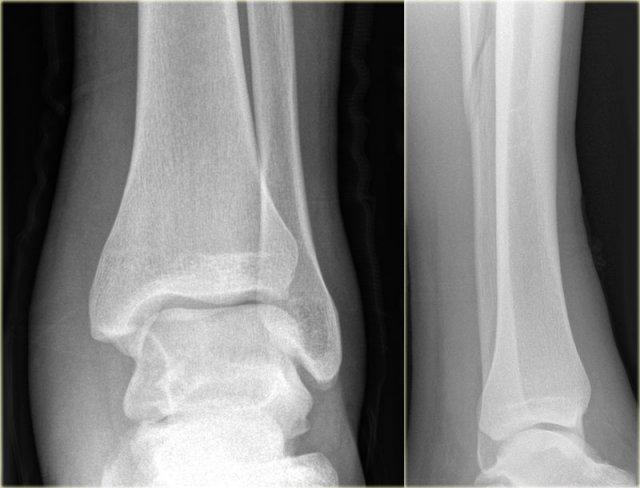

Các hình ảnh cho thấy gãy xương loại Weber A điển hình.

Tất cả đều là gãy xương giai đoạn 1.

Giai đoạn 2 cực kỳ hiếm gặp.

Chú ý hướng nằm ngang của các đường gãy.

Đây là các gãy xương kiểu giật đứt do kết quả của sự bong gân giật.